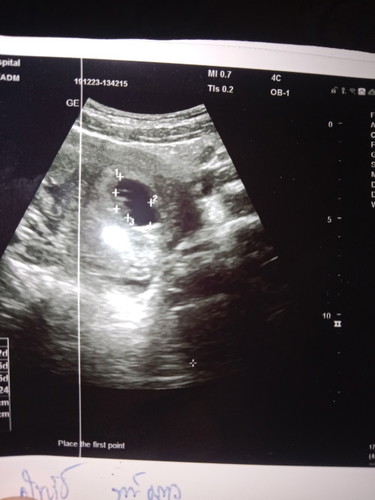

10วีคแต่พอไปซาวได้แค่7วีค5วันเองหมอบอกไม่ได้เสียงหัวใจหมอบอกเหมือนมีแค่ก้อนเนื้อหมอนัดอีก2อาทิตให้ไปซาวใหม่กังวลมากเลยเคยมีประวัตท้องลม3ท้องด้วย😰หมอบอกถ้ามีเวลาให้ไปซาวในเมืองจะได้ซาวทางช่องคลอดจะได้เห็นชัดขึ้น